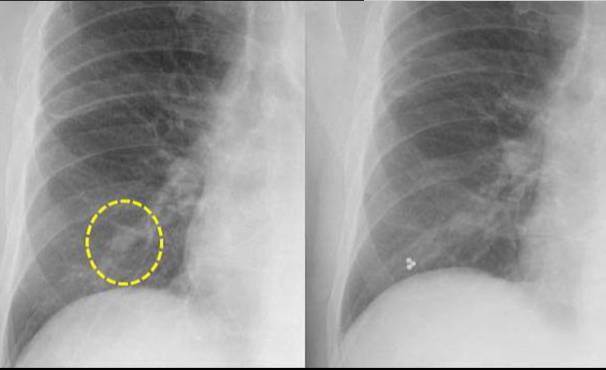

图文详解丨如何判断孤立性肺结节是良性还是恶性?

【讨论】30岁男性,体检发现右下肺结节影